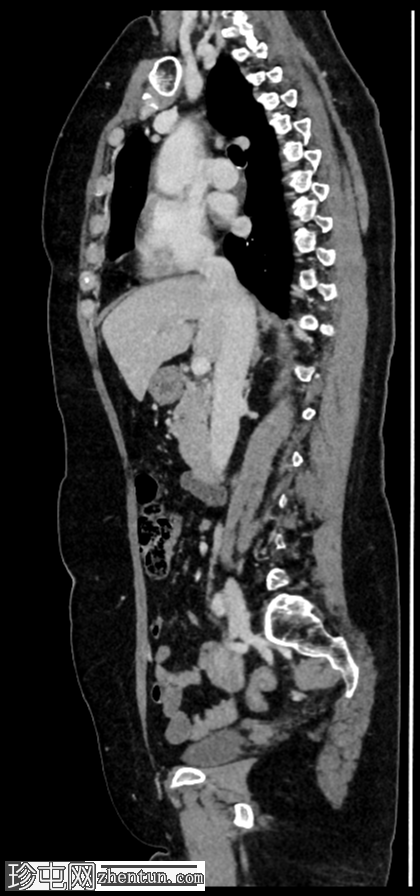

矢状位增强扫描

门静脉期

右肾上极前外侧可见一边界清晰、分叶状、部分外生性病变,大小约4.0 x 6.8 cm(轴位)。病变内侧为无强化囊性成分,直径2.3 cm(动脉期和门静脉期平均密度均为13 HU);外侧为强化实性成分,直径4.5 cm(动脉期和门静脉期平均密度分别为68 HU和78 HU)。病灶内可见多处小钙化灶。病灶毗邻肝右叶,但未见侵犯肝实质的证据。肾静脉和下腔静脉通畅。肾门水平可见数个小的主动脉腔静脉淋巴结和腔静脉后淋巴结,其中最大的腔静脉后淋巴结短轴直径为7毫米。

右肾中极前缘可见10毫米Bosniak II型囊肿,双侧肾盂旁可见囊肿。右肾下极可见两处肾皮质缺损。肝脏第8段可见5毫米囊肿。未见远处转移。L2椎体可见血管瘤。